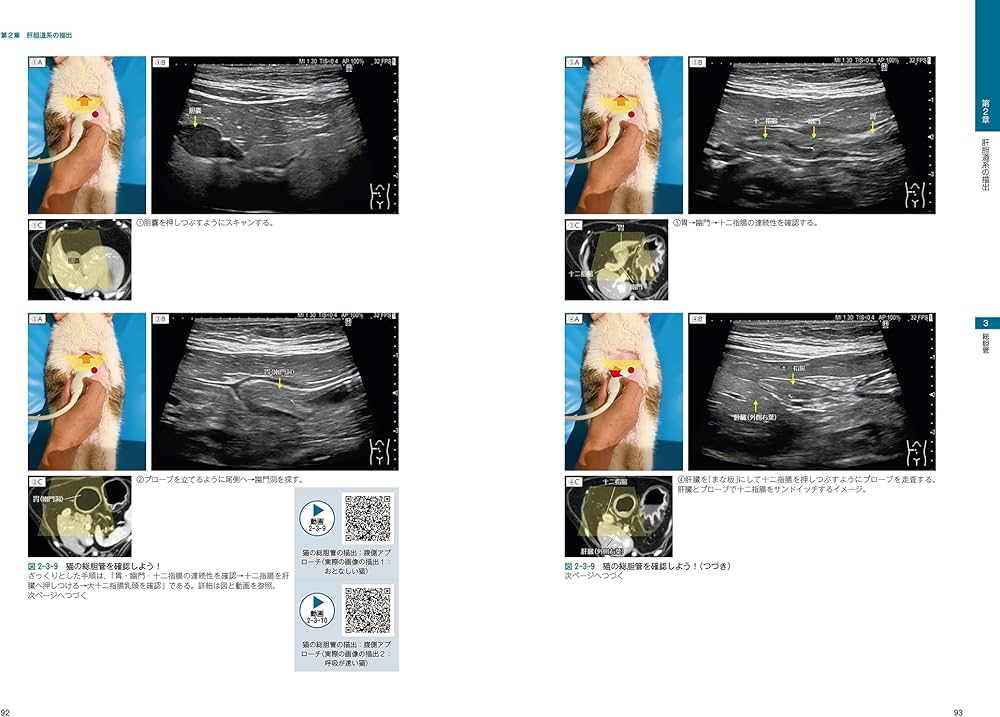

ご覧いただきありがとうございます。\r\r裁断済みとなっておりますので、購入の際はご注意ください。\r\r「ビジュアルと動画でわかる! 犬と猫の腹部超音波の描出レッスン 下巻」\r定価: ¥ 14,300\r注意⚠️\r・購入後裁断しました。スキャン時のスレ・ヨレ等はあるかもしれません。ScanSnapiX1600で問題なくスキャン出来ました。・裁断済みのため「全体的に状態が悪い」にしております。・カバーは裁断しておりません。\r高額な書籍になるため、商品説明はよくご確認の上ノークレームノーリターンにてよろしくお願いいたします。